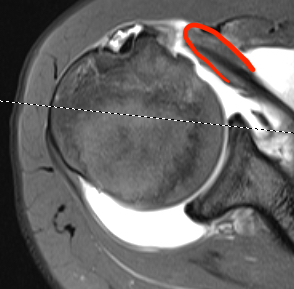

Perched long head of biceps with tear of upper border of subscapularis